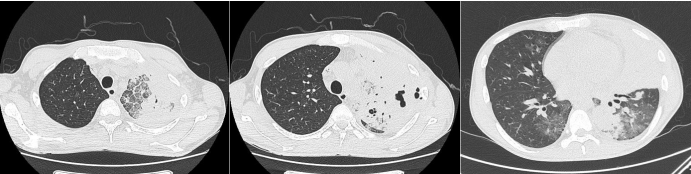

胸部CT

4月出现发热,体温38℃,5月咳黄色黏痰,体重下降15 kg,就诊于当地医院,检查提示WBC 1.83×109/L;胸部CT示:双肺多发病变伴纵隔淋巴结肿大;颈部淋巴结肿大。淋巴结穿刺考虑结核感染不除外,建议胸科医院排查,后排除结核,自服中药。

8月患者咳嗽再次加重,伴黄色黏痰,偶伴痰中带血丝,伴乏力,体重较5月下降10 kg,遂就诊于当地附属医院,完善气管镜检查、CT引导下肺穿刺活检考虑曲霉感染可能。骨穿提示骨髓增生异常综合征(MDS)可能。予以伏立康唑、亚胺培南、更昔洛韦抗感染治疗后,复查肺部CT感染灶未见明显好转。

患者为求进一步诊治于2021年9月18日就诊于我院门诊,以“社区获得性肺炎,肺曲霉病”收入我科。